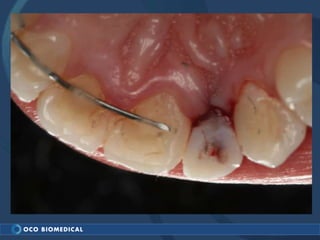

A 3.0mm dental implant was placed to replace congenitally missing maxillary lateral incisors. Dr. Tim Kosinski used a 1.8mm pilot bur and tissue punch to prepare the osteotomy site, then placed the implant by hand and seated it with a torque wrench. After ensuring the implant trajectory was within the restorative envelope, an acrylic coping was placed for temporary fabrication. At the 1 week post-op appointment, excellent soft tissue response and papilla formation were observed, and a final impression was taken to send to the lab for crown fabrication.